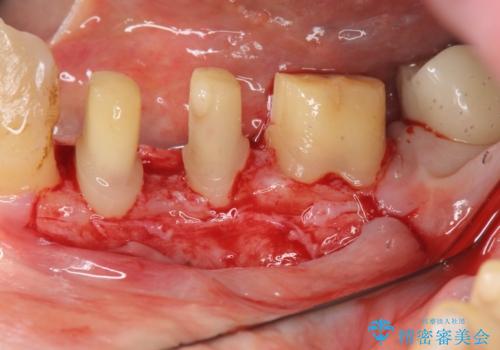

歯周病再生治療と歯周ポケット除去 歯周外科手術

がたつきの強い天然歯を矯正治療で整えたのち、再生治療、歯周ポケットを除去する歯周外科手術を行いました。

再生療法を行ったことで、抜歯をされてもおかしくなかった歯を、残すことができました。

- 外科手術のため、術後に痛みや腫れ、違和感を伴います

- 歯周組織再生治療は患者様の状態によって術後の経過が異なります(見た目が改善しない場合もあります)